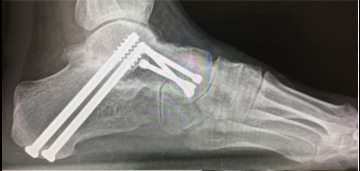

Double arthrodesis is a surgical procedure used to treat painful hindfoot arthritis or deformity by fusing two of the three major hindfoot joints, most commonly the subtalar and talonavicular joints. This approach preserves the calcaneocuboid joint while still providing significant correction and pain relief.

Double arthrodesis involves removing cartilage from the two affected hindfoot joints and positioning the foot in optimal alignment. The joints are stabilized using screws and/or plates to allow solid fusion.

The specific joints fused depend on the pattern of arthritis or deformity. Additional procedures may be performed to optimize alignment and balance.